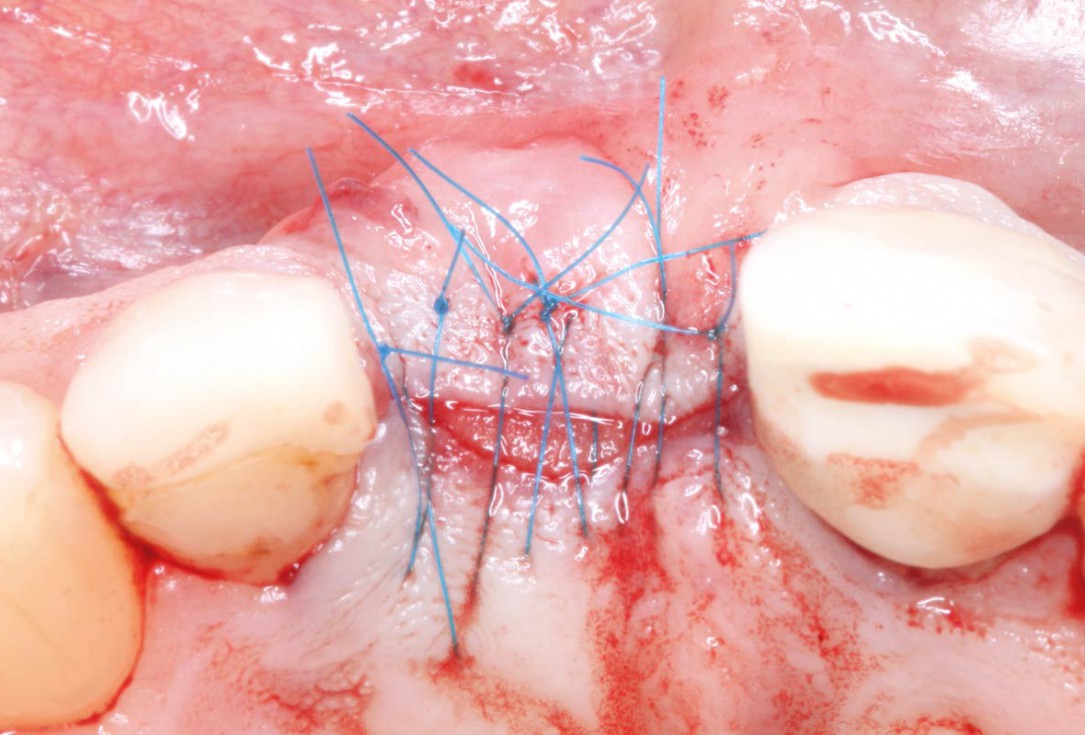

06/10 - Suturing; mucoderm® partially left exposed

Socket augmentation using mucoderm®, maxgraft® and Straumann® Emdogain® - Dr. A. Puišys